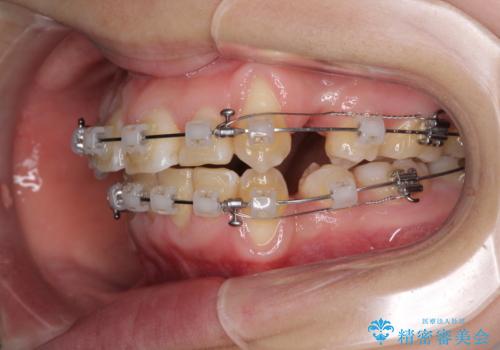

- クリアブラケット

- 2年1ヶ月

- 10-30回